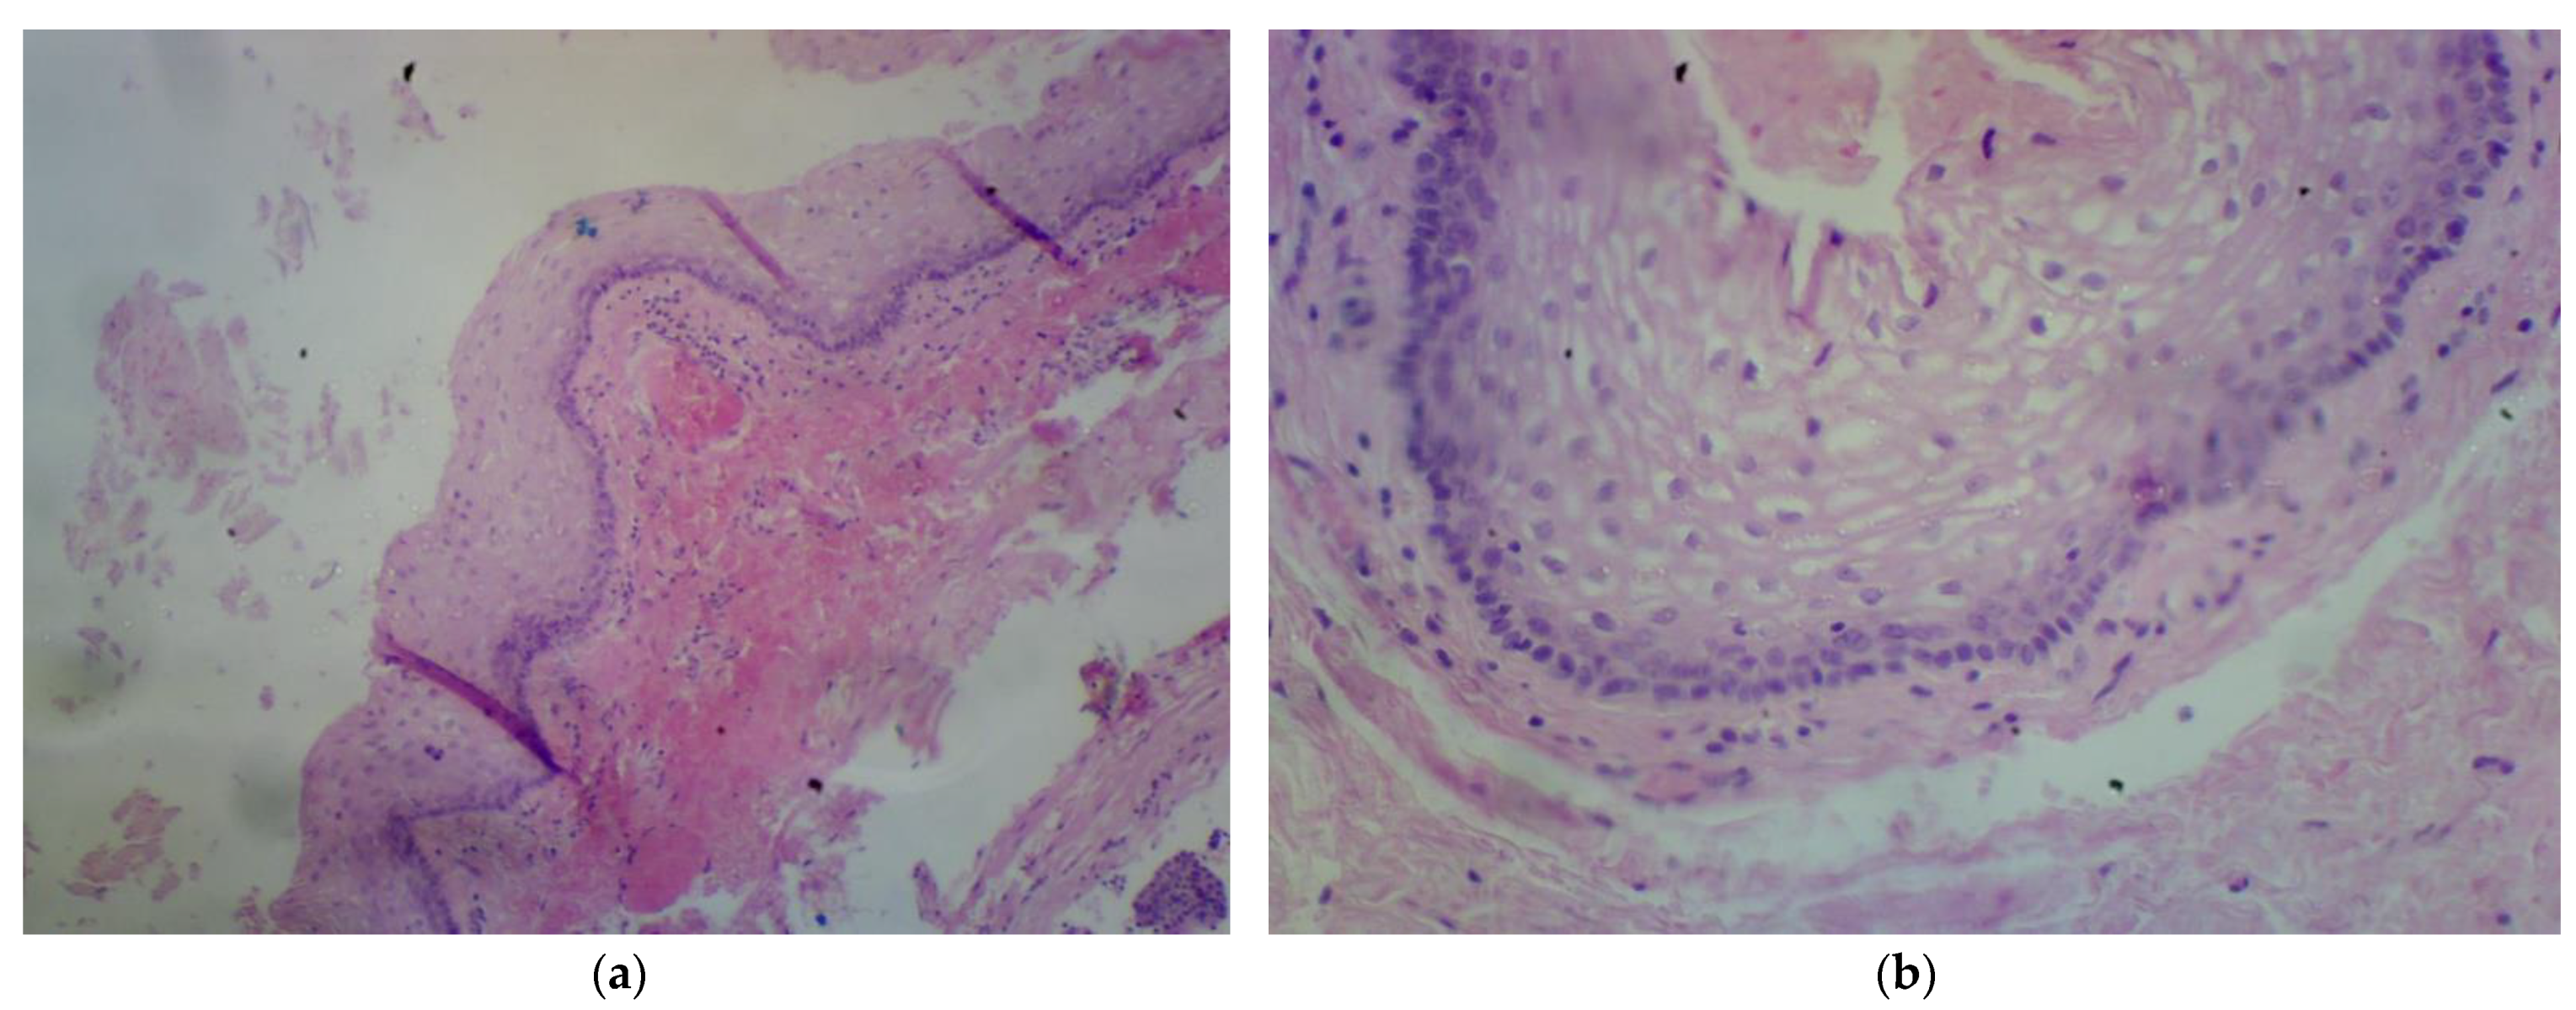

The second patient is a 36-year-old woman with a tumor of the lesser pelvis and endometriosis. In 2022, the patient started to experience pain in the sacral spine, which increased when she was sitting and after physical activity. The patient also complained about constipation and tenesmus. An ultrasound showed a tumor in the lesser pelvis. An MRI scan showed a cystic, multilocular tumor measuring 3.3 cm × 3.3 cm × 3.6 cm [Figure 3]. The signal had high intensity in the T1-weighted phase. The cyst pressured the rectum. The patient underwent unsuccessful laparoscopy and laparotomy in the Gynecology and Obstetrics Clinic.

Figure 3. Second patient MRI scan of lesser pelvis. Green arrow shows the cyst.